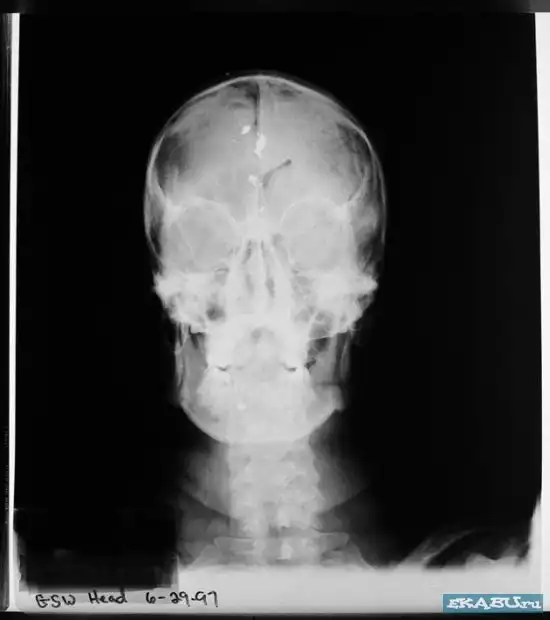

Рентгеновский снимок черепа после самоубийства выстрелом в голову.